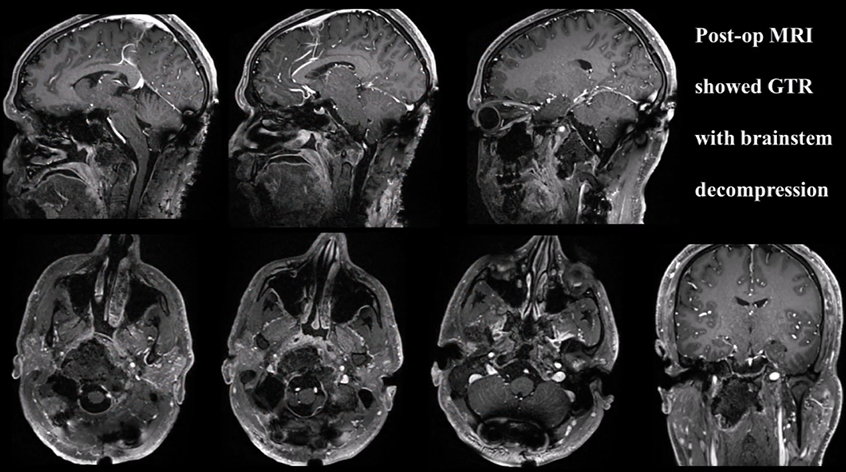

患者26歲,男,主訴頸部疼痛、嚴重吞咽障礙、雙側(cè)舌下神經(jīng)麻痹(右側(cè)完全麻痹伴舌萎縮,左側(cè)部分麻痹)。MRI和CT掃描(圖3A-C)顯示較大顱頸交界區(qū)脊索瘤,腫瘤較大直徑達10cm、瘤體積96.5cm³,腫瘤并向雙后外側(cè)延伸浸潤性生長,較多侵犯右側(cè),腫瘤延伸至椎前間隙、下斜坡、雙側(cè)枕骨髁、一頸椎C1的前弓以及C2的齒狀突,較大腫瘤壓迫腦干和雙側(cè)椎動脈移位,并向硬膜內(nèi)壓迫擴張。

手術(shù)記錄:福教授考慮腫瘤已經(jīng)導(dǎo)致顱頸交界區(qū)骨質(zhì)結(jié)構(gòu)的廣泛損害和侵蝕,術(shù)前評估手術(shù)后會出現(xiàn)顱頸不穩(wěn)定。因此,經(jīng)遠外側(cè)經(jīng)髁入路進行顯微鏡+神經(jīng)內(nèi)鏡雙鏡聯(lián)合切除腫瘤,然后枕頸融合術(shù)(OCF)。

使用Roy-Camille技術(shù)進行枕頸融合術(shù)(C0-C3-C4-C5),固定根釘以曲線方式橫向彎曲,為后續(xù)質(zhì)子治療創(chuàng)造一個無金屬的定位及治療通道。術(shù)后CT和MRI顯示腫瘤完全切除。病理證實為典型脊索瘤。在術(shù)后恢復(fù)中,患者吞咽功能好轉(zhuǎn)和頸部疼痛緩解。8周后,他接受了質(zhì)子治療。

▼術(shù)后MRI顯示腫瘤完全切除,且腦干解壓

A和B:術(shù)前CT掃描顯示顱頸交接區(qū)脊索瘤,侵犯斜坡-枕髁并呈溶骨性損害。C:術(shù)前MR顯示腫瘤較大延伸,并浸潤長入硬膜內(nèi)的腦實質(zhì)。D:術(shù)后CT顯示PMMA枕髁重建穩(wěn)定良好。E:術(shù)后三維CT顯示C0-C3-C4-C5枕頸融合穩(wěn)定,與根釘彎曲有利于PBRT治療。F:術(shù)后MR顯示全切腫瘤和腦干延髓占位壓迫得到解除。